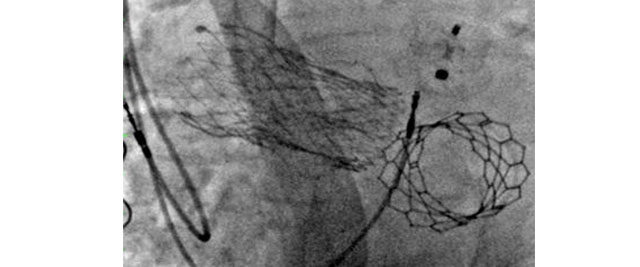

TAVI in a bicuspid aortic valve stenosis

05 Jul 2019 – From AICT-AsiaPCR 2019

Watch this LIVE demonstration from Clinique Pasteur (France) to learn about the case of a 81 years-old male patient with dyslipidemia referred to the hospital because of NYHA II shortness of breath related to a severe aortic stenosis. CT scan revealed a type I L-R bicuspid...